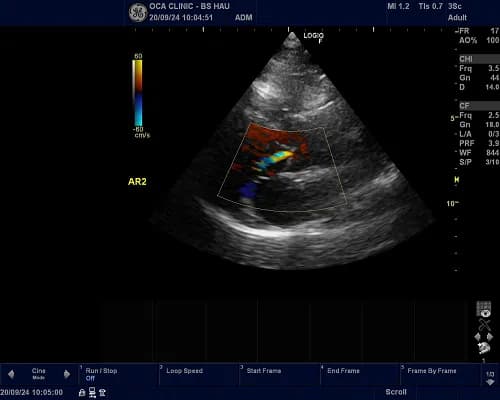

Siêu âm Doppler

Siêu âm Doppler dùng để kiểm tra lưu lượng máu, đo áp lực động mạch phổi . Bác sĩ có thể sử dụng siêu âm doppler màu để lập bản đồ hướng và tốc độ của các dòng máu trong tim.

Thông thường máu chảy về phía đầu dò xuất hiện màu đỏ, máu chảy ra có màu xanh.

Kết quả của siêu âm Doppler có thể kiểm tra, phát hiện một số bệnh tim, mạch máu và đánh giá cung lượng tim.

Hình ảnh sieu âm tim phát hiện bệnh lý hở van 2 lá

Siêu âm tim là giải pháp hiệu quả giúp bác sĩ chẩn đoán cũng như dễ dàng phát hiện ra các bệnh lý liên quan đến tim mạch như hở van tim, suy tim, nhồi máu cơ tim, viêm cơ tim,... Việc này giúp người bệnh có thời gian chuẩn bị tâm lý và nhanh chóng điều trị kịp thời giúp đảm bảo chất lượng sức khỏe trước khi xảy ra các tình trạng xấu hơn.